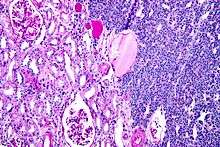

| Micrograph of a metanephric adenoma with structures reminiscent of those seen in papillary renal cell carcinoma. H&E stain. | |

Metanephric adenoma (MA)is a rare, benign tumour of the kidney, that can have a microscopic appearance similar to a nephroblastoma (Wilms tumours),[1] or a papillary renal cell carcinoma.

Metanephric adenoma is diagnosed histologically. The tumours can be located at upper pole, lower pole and mid-hilar region of the kidney; they are well circumscribed but unencapsulated, tan pink, with possible cystic and hemorrhagic foci. They show a uniform architecture of closely packed acinar or tubular structures of mature and bland appearance with scanty interposed stroma.[3][4][5][6][7] Cells are small with dark staining nuclei and inconspicuous nucleoli. Blastema is absent whereas calcospherites may be present. Glomeruloid figures are a striking finding, reminiscent of early fetal metenephric tissue. The lumen of the acini may contain otherwise epithelial infoldings or fibrillary material but it is quite often empty. Mitoses are conspicuously absent.[3][4][5][6][7] In the series reported by Jones et al. tumour cells were reactive for Leu7 in 3 cases of 5, to vimentine in 4 of 6, to cytocheratin in 2 of 6, to epithelial membrane antigen in 1 of 6 cases and muscle specific antigen in 1 of 6.[8] Olgac et al. found that intense and diffuse immunoreactivity for alpha-methylacyl-CoA racemase (AMACR) is useful in differentiating renal cell carcinoma from MA but a panel including AMACR, CK7 and CD57 is better in this differential diagnosis.[9] Differential diagnosis may be quite difficult indeed as exemplified by the three malignancies initially diagnosed as MA that later metastasized, in the report by Pins et al.[10]